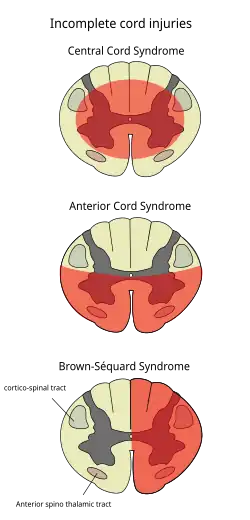

Central cord syndrome

Incomplete lesions of the spinal cord: Central cord syndrome (top), Anterior cord syndrome (middle), and Brown-Séquard syndrome (bottom)

Central cord syndrome, almost always resulting from damage to the cervical spinal cord, is characterized by weakness in the arms with relative sparing of the legs, and spared sensation in regions served by the sacral segments.[25] There is loss of sensation of pain, temperature, light touch, and pressure below the level of injury.[26] The spinal tracts that serve the arms are more affected due to their central location in the spinal cord, while the corticospinal fibers destined for the legs are spared due to their more external location.[26]

The most common of the incomplete SCI syndromes, central cord syndrome usually results from neck hyperextension in older people with spinal stenosis. In younger people, it most commonly results from neck flexion.[27] The most common causes are falls and vehicle accidents; however other possible causes include spinal stenosis and impingement on the spinal cord by a tumor or intervertebral disc.[28]

Anterior spinal artery syndrome

Anterior spinal artery syndrome also known as anterior spinal cord syndrome, due to damage to the front portion of the spinal cord or reduction in the blood supply from the anterior spinal artery, can be caused by fractures or dislocations of vertebrae or herniated disks.[26] Below the level of injury, motor function, pain sensation, and temperature sensation are lost, while sense of touch and proprioception (sense of position in space) remain intact.[29][27] These differences are due to the relative locations of the spinal tracts responsible for each type of function.

Brown-Séquard syndrome

Brown-Séquard syndrome occurs when the spinal cord is injured on one side much more than the other.[30] It is rare for the spinal cord to be truly hemisected (severed on one side), but partial lesions due to penetrating wounds (such as gunshot or knife wounds) or fractured vertebrae or tumors are common.[31] On the ipsilateral side of the injury (same side), the body loses motor function, proprioception, and senses of vibration and touch.[30] On the contralateral (opposite side) of the injury, there is a loss of pain and temperature sensations. If the injury is above pyramidal decussation there is contralateral hemiplegia, at the level of decussation there is completed motor loss on both sides and below pyramidal decussation there is ipsilateral hemiplegia.

[28][30]Spinothalamic tracts are in charge for pain and temperature sensation and because these tracts cross to the opposite side and above the spinal cord there is loss on the contralateral side.[32]